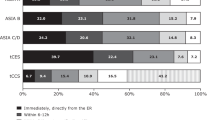

Patient demographics and injury characteristics

A total of 105 patients underwent phenol neurolysis in our institution between April 2017 to August 2018. Among these, 66 patients with SCI were included in this study, and 39 subjects with non-SCI diagnoses were excluded. There were 70% males with a mean (SD) age of 50 [17] years (Table 1). The etiology of SCI for most patients (88%) was traumatic and cervical level (61%) of injury was most common. Among cervical traumatic SCI, the majority of the people in the study had a neurological level of C1–C4 and AIS A–C impairment (Table 1). For the 12% non-traumatic SCI cases, diagnoses included transverse myelitis, myelopathy, and non-progressive mass lesions such as arachnoid cyst, epidural hematoma, and ependymoma. Among 66 patients, 52% had private insurance or private funding, and 46% had government funding (Medicare and Medicaid).

Visit and injection details

There were 102 encounters, of which 61% were in the outpatient setting, and 39% were in the inpatient setting (Table 2). The majority of treatments (n = 92, 90%) were performed by a physiatrist or trainees under the supervision of same physiatrists with over ten years of experience with the procedure. Electrical stimulation and ultrasound guidance were utilized in nearly all patient visits (n = 99, 97%). During the 102 clinical encounters, a total of 303 nerve or motor branches were injected.

There were 66 unique patients. Twenty patients received repeat injections during this time frame; 10 had phenol neurolysis twice, 6 were injected three times, 2 were injected four times, and 2 were injected five times either same or different nerves during the study time frame. Phenol neurolysis was most commonly injected in proximal large muscle groups compared to smaller distal muscle groups. Approximately two-thirds of the injections (n = 201, 66%) involved the lower extremity. The obturator nerve and motor branches (n = 101, 33%) to the hip adductors were the most commonly injected lower extremity nerves. Other common targets of the lower extremity were tibial motor branches to the gastrocnemius and soleus muscles (Table 3). One-third of the phenol neurolysis injections (n = 102, 34%) were performed on the upper extremities, and the most common targets included the medial and lateral pectoral nerves (n = 71, 23%) followed by musculocutaneous motor branches to the biceps brachii and brachialis muscles (Table 3).

A median (IQR) of 2 [2,3,4] nerves were injected during each encounter with a median (IQR) of 4 [2,3,4,5,6] ml dose in total per encounter. The total dose per encounter ranged from 0.2 to 20 ml. However, 93% of the patients received a total dose of ≤10 ml per encounter. During each encounter, phenol median dose (IQR) was 1.5 (1.0–2.3) ml per nerve or nerve branch. At the time of the clinical encounter, the most commonly reported concomitant treatment was oral baclofen (n = 79, 77%) followed by botulinum neurotoxin (n = 64, 63%).